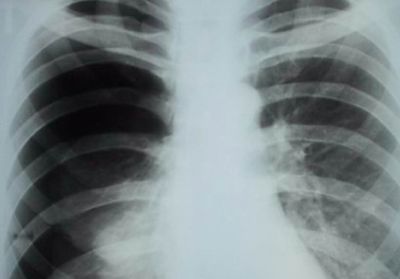

Пневмония

Характер и локализация боли

Правостороннее воспаление легкого характеризуется тупой болью в правом боку, локализованной преимущественно в подреберье.

При длительном течении заболевания боль ощущается в груди и спине со стороны пораженного органа.

Диагностика и лечение

При возникновении описанных выше симптомов необходимо обратиться к пульмонологу, который проведет осмотр и сбор анамнеза и назначит дополнительные диагностические процедуры, включающие:

- рентгенографию;

- КТ;